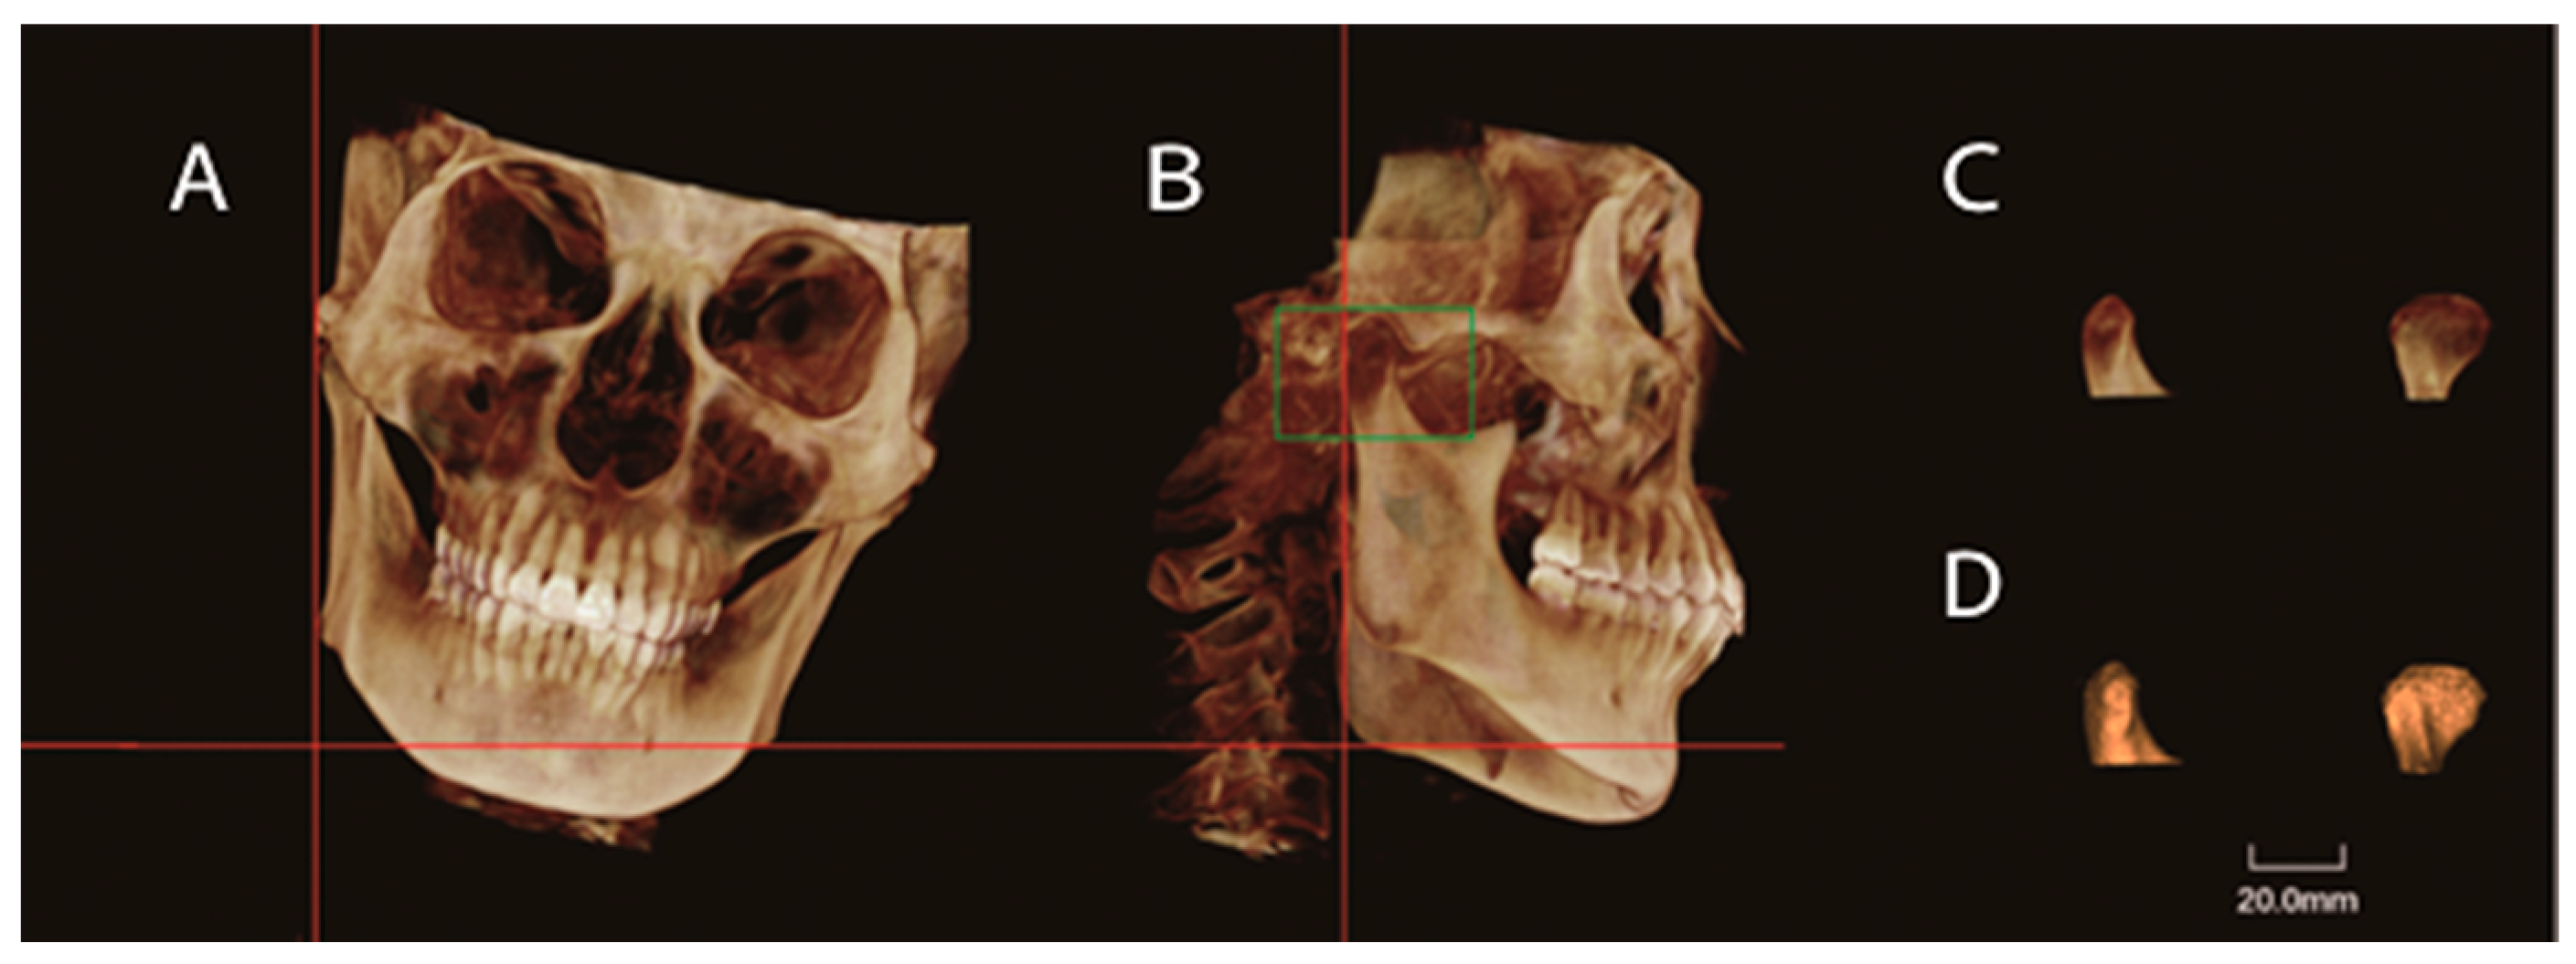

| Maximal sectional area | Smax | Maximal sectional area of the condyle |

| Condylar volume (mm3) | 1626.74 ± 406.71 | 977.49 ± 302.50 *** | 893.74 ± 209.87 *** | 1442.79 ± 459.13 |